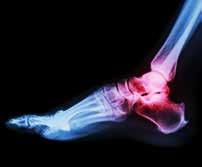

Fractures, Arthritis and More

The new facility will allow the doctors at SFISM to treat many ailments in-house, eliminating the need for a trip to the hospital. They diagnose and treat all foot, ankle and leg fractures in adults and children. They also treat foot and ankle arthritis and many cartilage injuries.